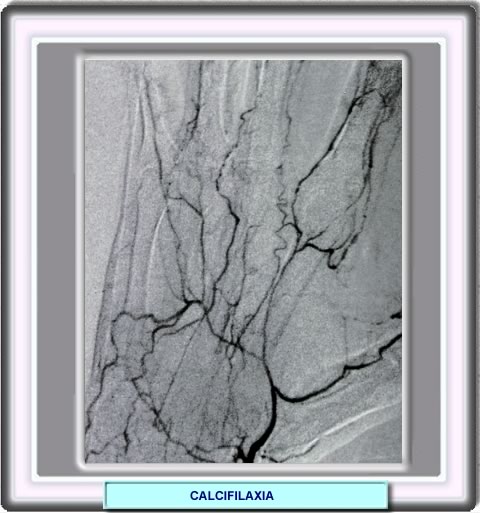

CALCIFILAXIA

Las radiografías y las angiografias de las áreas afectadas muestran la calcificación vascular